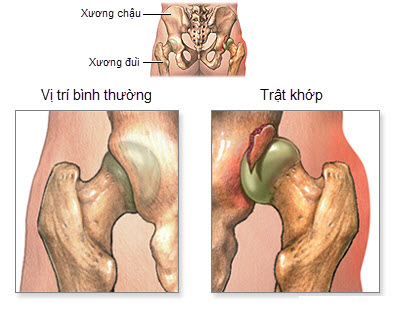

Trật khớp háng là tình trạng chỏm xương đùi trật ra khỏi vị trí đúng của khớp háng.

Tùy theo vị trí trật mà trật khớp háng có thể được phân thành một số nhóm sau:

- Trật khớp về phía sau;

- Trật khớp ra phía trước;

- Trật khớp tại trung tâm